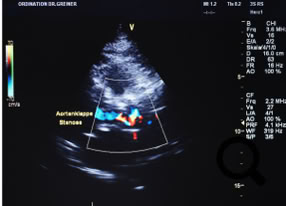

Sklerose der Aortenklappe

Zum Vergrößern auf Bild klicken